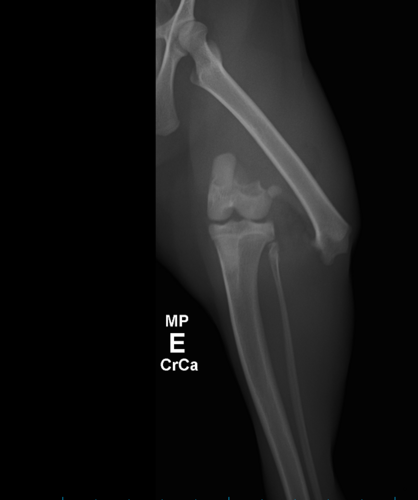

Meu nome é Kelly, eu adotei uma linda gatinha a Sophia, tem 7 meses de idade, e esses dias ela fugiu de casa, mesmo que a janela estava com proteção, estava no trabalho, quando cheguei em casa ela não estava, fui a sua procura e a encontrei machucada com a Pata traseira fraturada no fêmur com algumas lesões no corpo, não sei o que aconteceu com ela, não conseguir vaga no hospital público, gostaria de ajuda para pagar a cirugia dela não tenho condições de pagar. 🥺😢.

Sophia

SRD,7 meses de idade ♥️